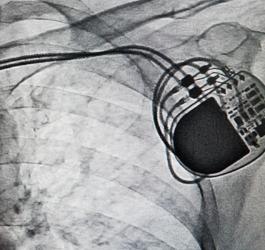

- Kardiologia